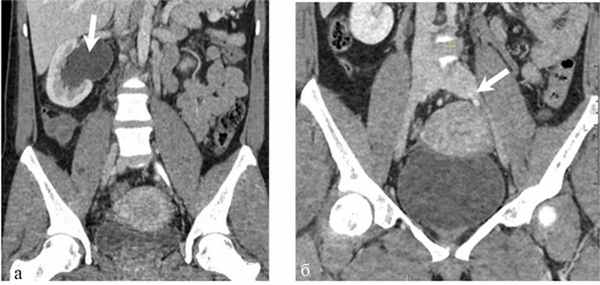

В клинике больная дообследована. В анализах крови и мочи значимых изменений не обнаружено. Помимо общеклинического обследования, выполнено трансабдоминальное и трансвагинальное ультразвуковое ангиосканирование (УЗАС), по результатам которого обнаружены расширение параметральных вен до 10 мм, маточных вен до 7 мм, правой гонадной вены до 8 мм, патологический рефлюкс крови по этим сосудам. Ультрасонографических признаков патологии подвздошных вен не выявлено. В ходе выполнения мультиспиральной компьютерной томографии (МСКТ) с контрастным усилением диагностированы правосторонняя пиелоэктазия до 50×28 мм, расширение мочеточника в средней и нижней трети до 15 мм, сужение просвета левых подвздошных вен, расширение правой гонадной вены (рис. 1). Рис. 1. Компьютерные томограммы пациентки М. а — расширение правой почечной лоханки; б — стеноз левой общей подвздошной вены (указано стрелками). Органической патологии органов малого таза, забрюшинного пространства не выявлено.